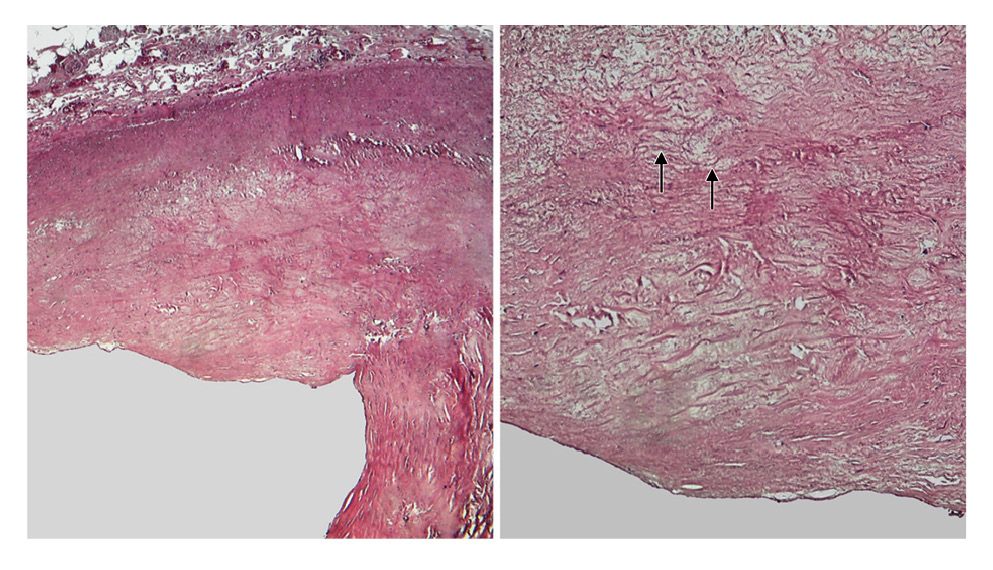

Рис. 5. Микрофотография левой КА у пациента с ИМ 2-го типа. Морфологические признаки атеросклероза, просвет артерии уменьшен более чем наполовину за счет утолщения интимы. Интима содержит плотную волокнистую ткань. В атрофированной медии обнаруживается эозинофильный материал (стрелки) в форме полумесяца. Окраска гематоксилином и эозином, ×40 (слева) и ×100 (справа).